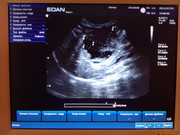

Здравствуйте, у кота по узи какое-то новообразование около поджелудочной, желчного и печени. Подскажите пожалуйста, на что это похоже? Есть только фото с экрана.

Здравствуйте! Очень сложно по картине понять, лучше короткое видео. Определяется образование неправильной формы, кистозной структуры, наиболее вероятно а поджелудочной железе, но объективно, нельзя исключить патологию желчных протоков.